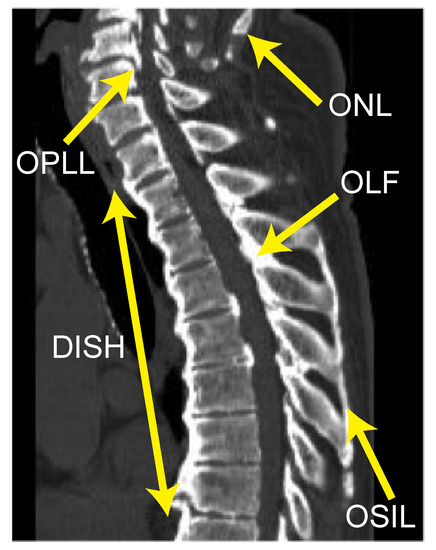

3.3. Case Presentation